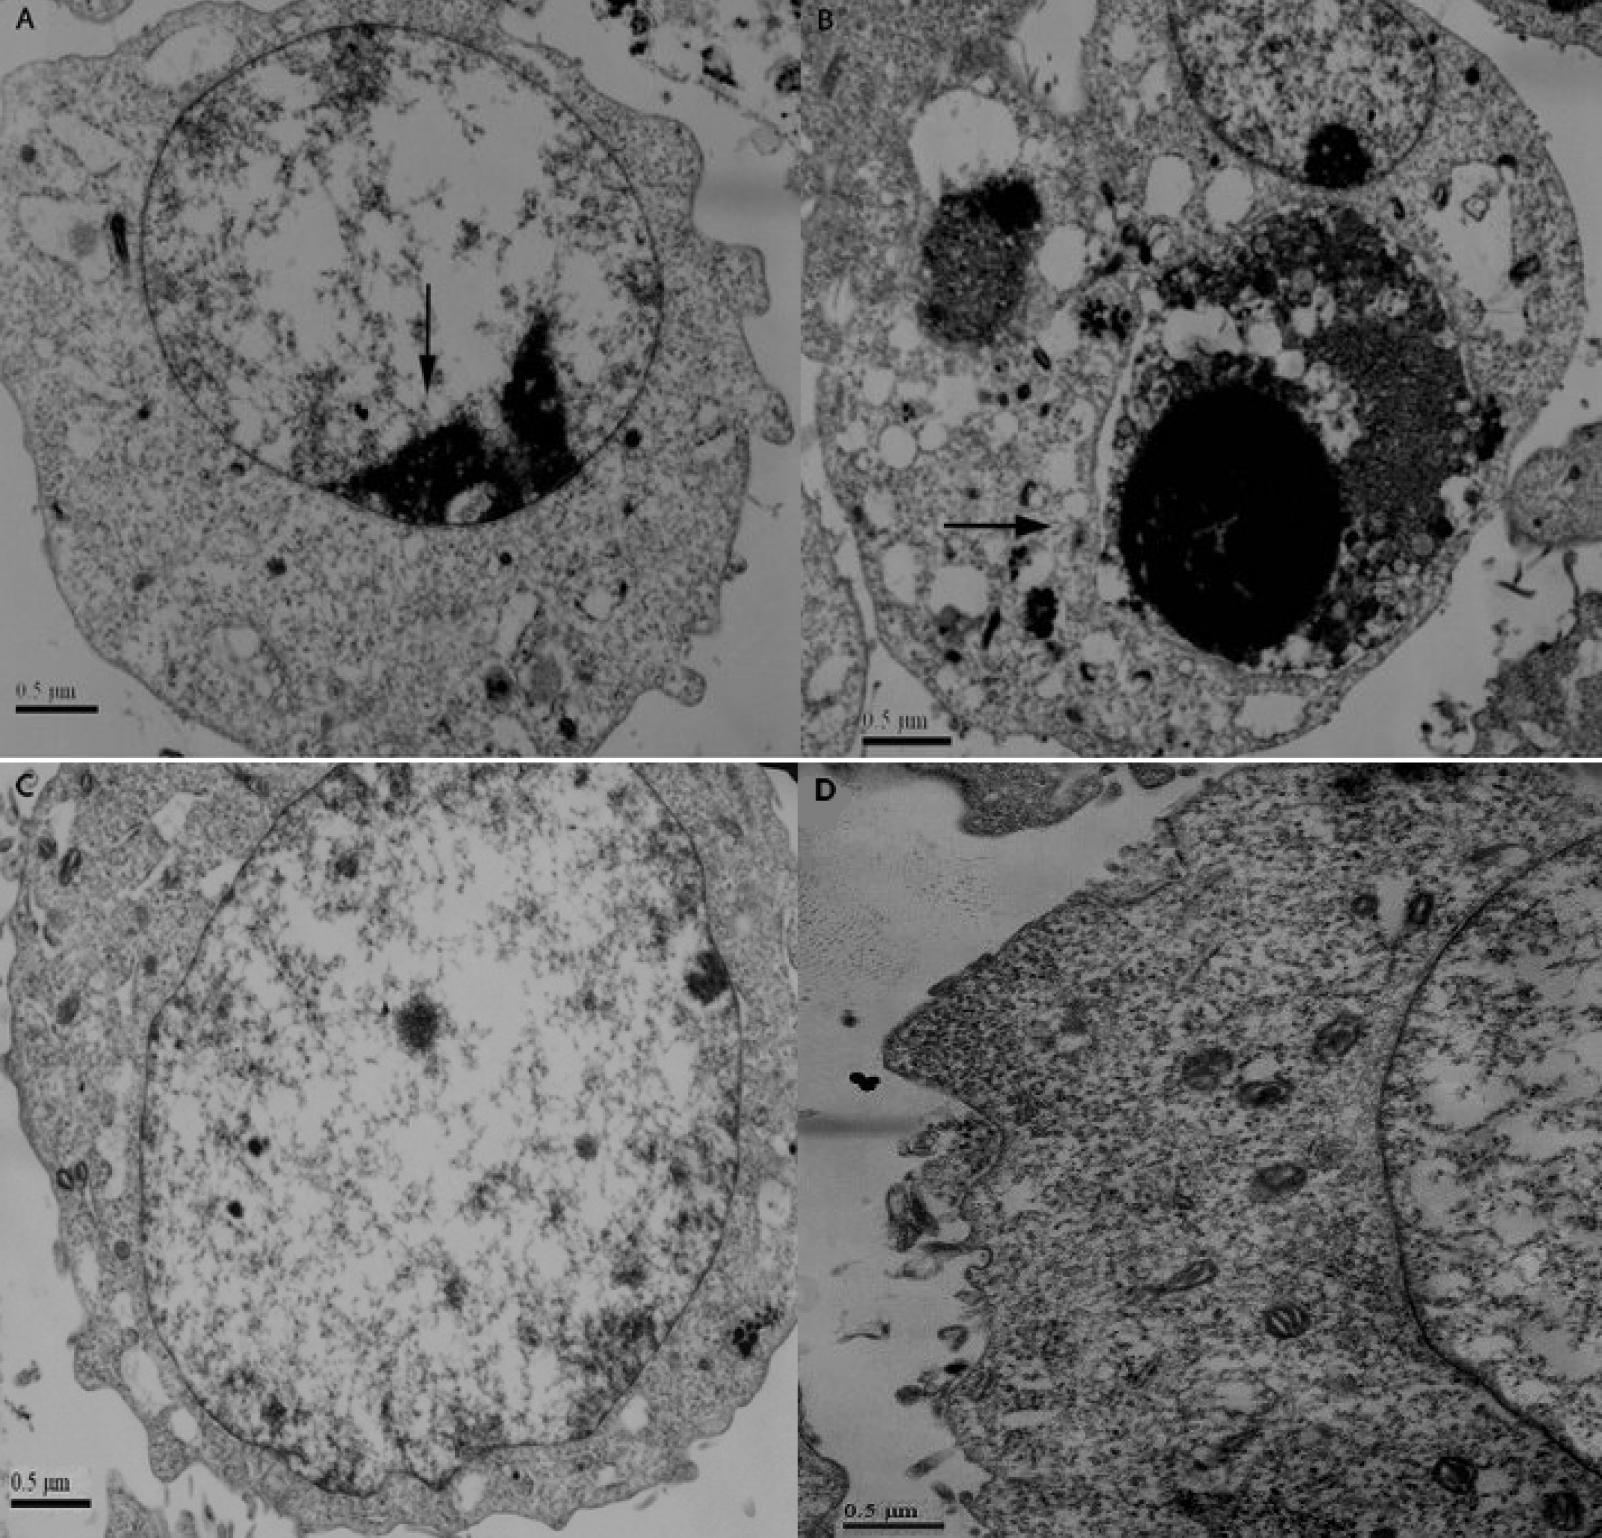

Figure 4. Electron microscopy showed

apoptosis in RGC-5 cells after stable transfection of

sihoptineurin-3. A: Nuclear heterochromatin margination,

partial membrane dissolution, rough endoplasmic reticulum

expansion, and mitochondrial reduction were observed in

sihoptineurin-3 RGC-5 cells. B: Mitochondrial outer

membrane damage, cell membrane partial dissolution, and

apoptotic bodies were observed in sihoptineurin-3 RGC-5 cells. C,

D: In sihoptineurin-NC RGC-5 and blank cells, we observed

nuclear membrane integrity, with organelles enriched in

cytoplasm.